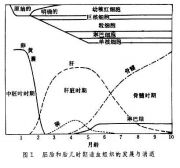

| 2021年7月26日 (一) 20:01 | 胚胎和胎儿时期造血组织的发展和消退.jpg (文件) |  |

26 KB | 77921020 | Uploaded with SimpleBatchUpload | 3 |